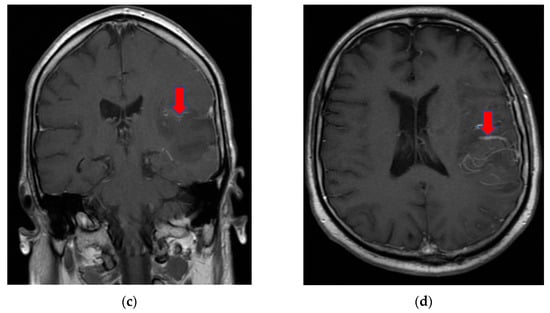

On day eight, the patient became comatose with altered neurological status and was intubated, with mechanical ventilation in the intensive care unit. He required i.v. fluids, pressors, ceftriaxone, vancomycin, and antifungals due to concerns regarding sepsis. A CT of the brain was obtained in light of the acute hemorrhage of intraparenchymal fronto-parieto-temporal lobes, showing important edema (Figure 4).

Figure 4.

(a,b), Brain-CT showed acute hemorrhage of intraparenchymal fronto-parieto-temporal lobes with important edema and ventricular extension.